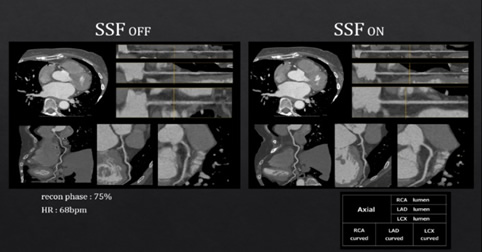

Snap Shot Freeze

自動で冠動脈の静止画像を再構築する動態アルゴリズムであり、前後約60msecのデータから3次元的に解析することでモーションアーチファクトの大幅な低減が可能となった。(図4)

201704_voice_img_ct_02_05.jpg

図4. SnapShot Freeze